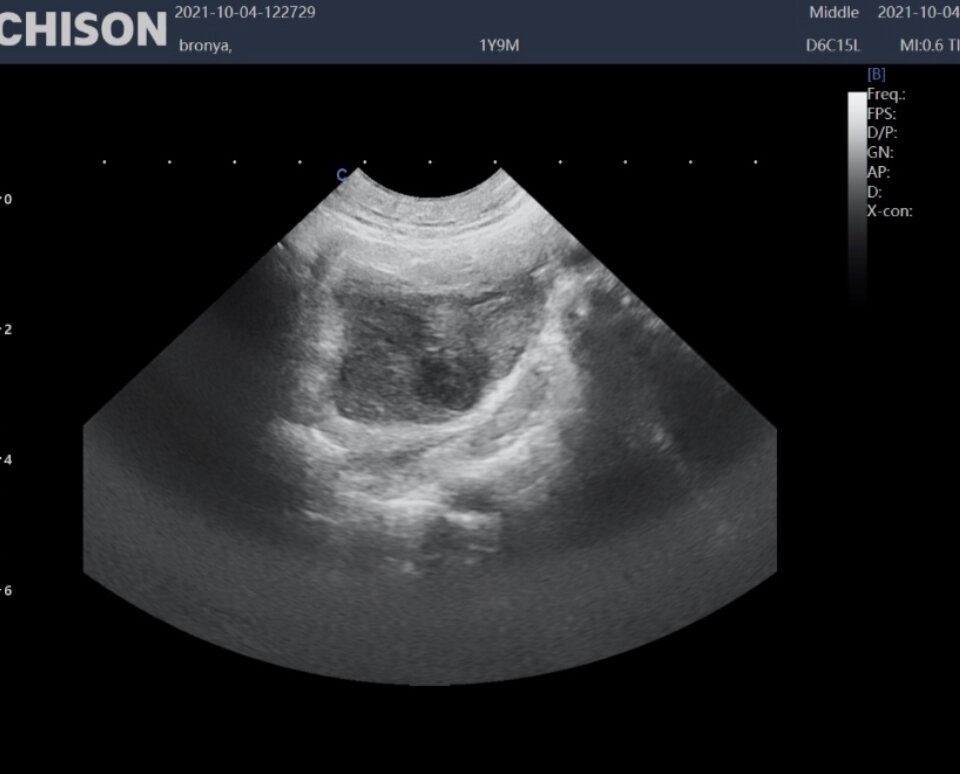

Структура в области левого яичника

Культя в области тела матки